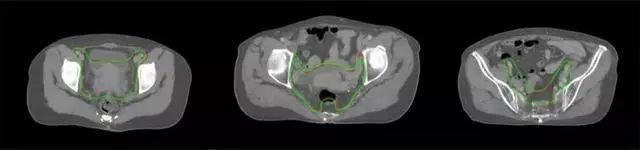

四、放射治療智能勾畫軟件

放射治療,簡稱放療,是治療腫瘤主要手段之一,利用放射線破壞照射區(qū)(靶區(qū))的細(xì)胞,使腫瘤細(xì)胞停止分裂直至死亡,醫(yī)生通常把放射治療形象的比喻為“打靶”,放療前精準(zhǔn)勾畫腫瘤靶區(qū)范圍是腫瘤放射治療的關(guān)鍵步驟。傳統(tǒng)的靶區(qū)勾畫醫(yī)生會根據(jù)患者多張CT、MRI影像片憑借經(jīng)驗(yàn)進(jìn)行,比較耗時,治療的病人數(shù)量也有限,且靶區(qū)勾畫缺少行業(yè)統(tǒng)一的規(guī)范和標(biāo)準(zhǔn),無法達(dá)到同質(zhì)化,勾畫精確度不理想。

技術(shù)原理

基于深度學(xué)習(xí)人工智能的放療靶區(qū)智能勾畫技術(shù)和自動計(jì)劃技術(shù),基于全面的市場調(diào)研和臨床專業(yè)意見,采用獨(dú)創(chuàng)的基于小樣本量的人工智能算法,實(shí)現(xiàn)放療靶區(qū)和危及器官的快速全自動勾畫。

產(chǎn)品優(yōu)勢

縮短至幾分鐘內(nèi)便可完成,大幅提升了放療效率,且人工智能平臺完成的靶區(qū)勾畫可基本滿足臨床醫(yī)生需求,專家只需審核時細(xì)微調(diào)整,可顯著提高靶區(qū)勾畫的規(guī)范化及精準(zhǔn)度,讓放療智能化,標(biāo)準(zhǔn)化。可覆蓋食管癌、鼻咽癌、直腸癌、宮頸癌、肺癌等多種病種。